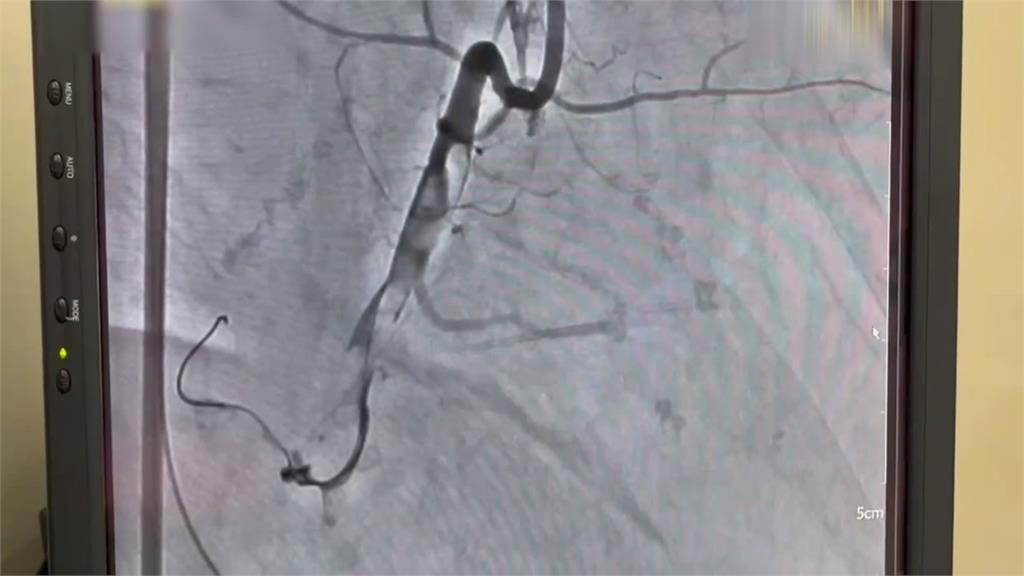

鬼門關前走一回!「葉克膜+心導管手術」存活率達55%(圖/翻攝畫面)

單靠CPR遠遠不足,送往醫院途中,救護人員為病患,進行10次AED電擊,到院時,心電圖顯示"致命性心律不整"。院方緊急裝上葉克膜,來維持病患的心跳與血液循環,爭取時間進行"心導管手術",打通被血栓堵住的血管,與死神搏鬥,成功搶回一命。根據統計,病人倒下6分鐘內如果即時獲得cpr急救,可以減少大腦損傷並且提高3倍存活率。不過每延遲一分鐘,存活率就會下降7%。如果在心跳停止時,"葉克膜"及時介入,存活率高達55%,像這名先生到院前就ohca,緊急實施"葉克膜心肺術"搶救,存活率有46%,倒下後的黃金幾分鐘,就可能替後續醫療爭取關鍵時間。